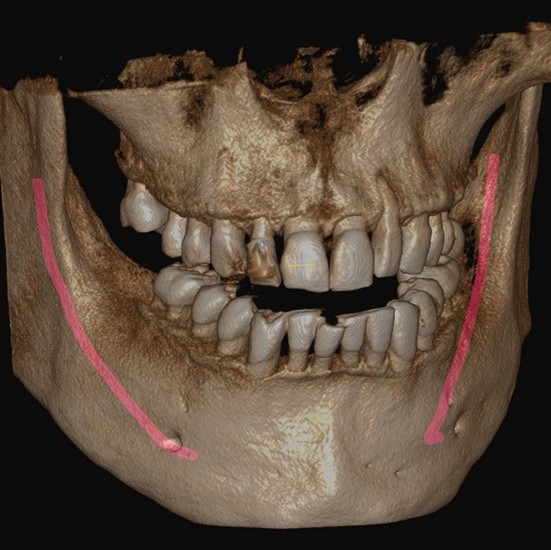

Planificarea implantului asistată de Inteligență Artificială (AI)

Rainbow™ CT integrează funcții avansate de Inteligență Artificială pentru a automatiza și simplifica sarcinile de rutină. De la identificarea poziției dinților lipsă până la stabilirea poziției inițiale a implantului și coroanei, AI-ul Dentium asigură o planificare eficientă și precisă a tratamentelor.

Implant/Coroană: Inteligența Artificială Dentium detectează automat poziția dinților lipsă și stabilește poziția inițială a implantului și coroanei pentru a simplifica planificarea implantului.

Nerv: Identificarea canalului nervului alveolar inferior se face în doar 15 secunde. Inteligența Artificială Dentium asigură un diagnostic mai precis și de încredere.

Arcada: Algoritmul AI generează automat linia arcadei în doar câteva secunde, cu o precizie ridicată.